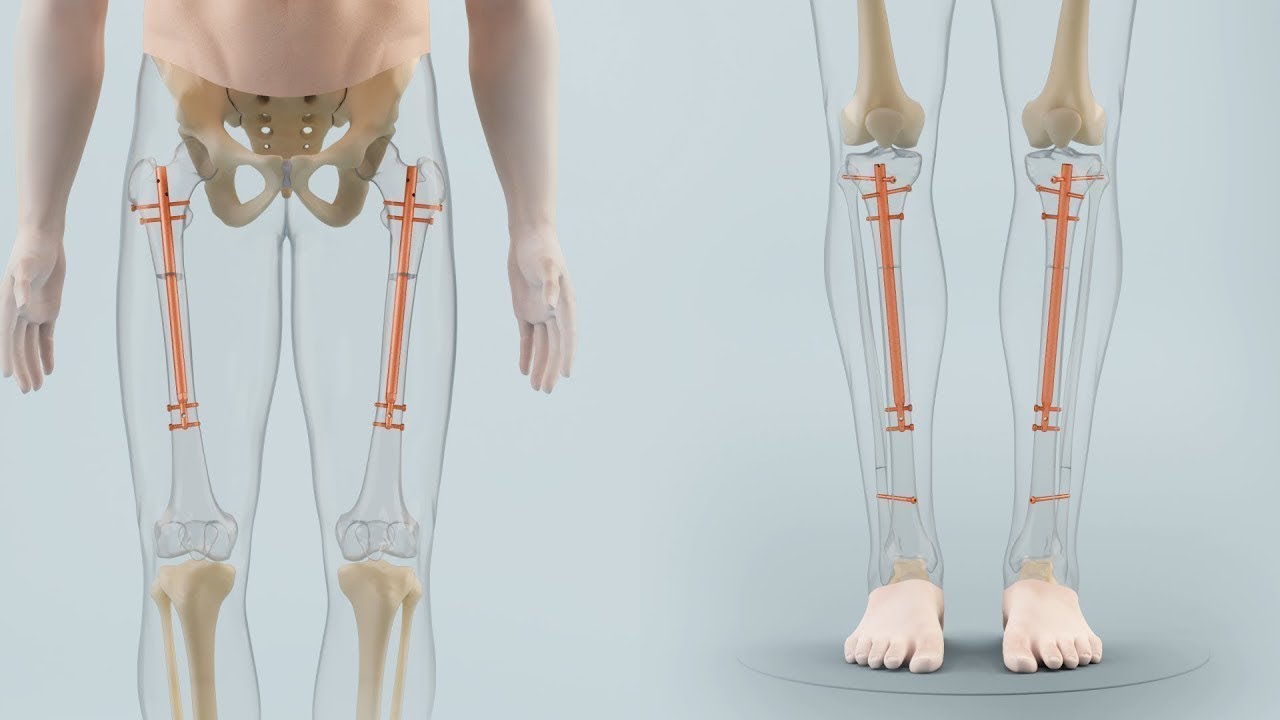

back because they're high or at least they think that it's holding them back yeah and there's a large part is about that once the story is in your head that you are being held back by it then you almost have to solve it otherwise you oh actually how bad by it but that's true with a lot of these things so I Googled the side effects and it's awful things so nerve damage muscle damage as a result to like potentially to get that result yeah I can imagine trying to stretch trying to walk again you have

is other limbs not going to be out of proportion right because like when you're a small person you often have like I have tiny hands I have you know my arms are also like not long as some another woman who is five at seven so are his arms now got not gonna be out for it's stuff like that that just I think this is so gone to the extreme and he seems so happy and sweet and attractive even without being six foot I just don't know I don't know if it's worth it obviously for him